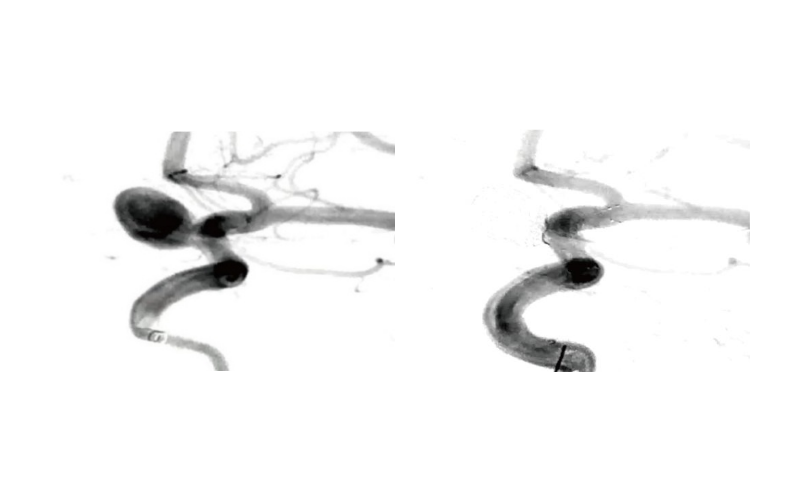

Available in a full range of helical and complex configurations, the Perdenser® Embolic Coil System provides complete solutions for framing, filling, and finishing, ensuring precise delivery in diverse clinical scenarios.

The first loop is designed at 75% of the nominal diameter, significantly reducing the risk of coil prolapse and ensuring safer deployment.

The optimized Ω open-loop design allows the coil to adapt naturally to aneurysms of any shape, achieving stable framing and dense, concentric filling for effective occlusion.